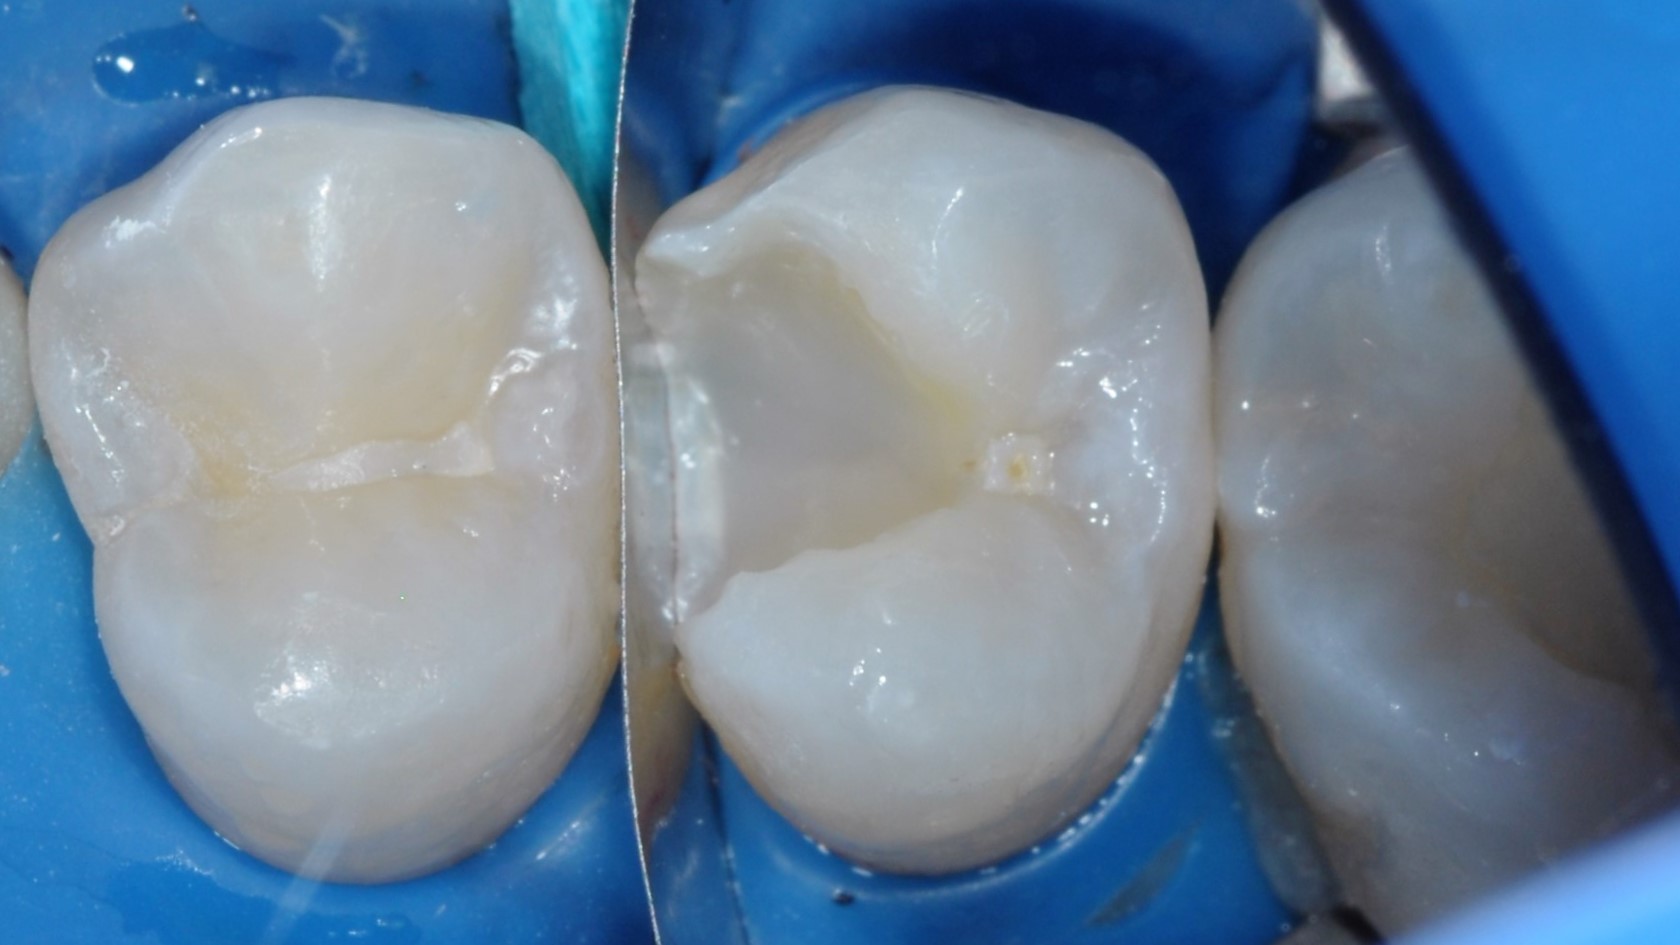

Leczenie zachowawcze zęba 15 rozpoczęto od testu żywotności (reakcja na bodziec zimny prawidłowa). Wykonano znieczulenie nasiękowe oraz izolację pola zabiegowego koferdamem (Rubber-Dam, Cerkamed) (ryc. 1). Ubytek opracowywano zgodnie z wytycznymi Europejskiego Towarzystwa Endodontycznego (European Society of Endodontology – ESE) w sprawie leczenia próchnicy głębokiej i obnażeń miazgi (1). W pierwszej kolejności, w powiększeniu, przy użyciu mikroskopu, wiertłem diamentowym na końcówce przyspieszającej usunięto próchnicowo zmienione szkliwo. Następnie wiertłem różyczkowym na mikrosilnik usunięto zainfekowaną bakteryjnie zębinę na peryferiach ubytku (infected dentine, soft dentine). Zbliżając się do komory zęba, zmieniono wiertło na sterylne i na niskich obrotach usuwano kolejne partie zębiny zainfekowanej. Podczas końcowej fazy opracowania ubytku doszło do próchnicowego obnażenia miazgi (obnażenie miazgi klasy II według ESE) (1) (ryc. 2). Zębinę zdemineralizowaną (affected dentine, firm dentine) pozostawiono w dnie ubytku. Krwawienie z miejsca obnażenia zahamowano sterylną gąbką, nasączoną roztworem 0,9-procentowym NaCl, uciskając przez 5 minut. Obnażenie zaopatrzono materiałem na bazie MTA (BIO MTA +, Cerkamed) i pozostawiono do wstępnego związania przez 12 minut (ryc. 3).

Ryc. 1. Sytuacja początkowa.

Ryc. 2. Próchnicowe obnażenie miazgi.

Ryc. 3. Przykrycie bezpośrednie (BIO MTA +, Cerkamed). Na ścianie dokomorowej widać firm dentine.